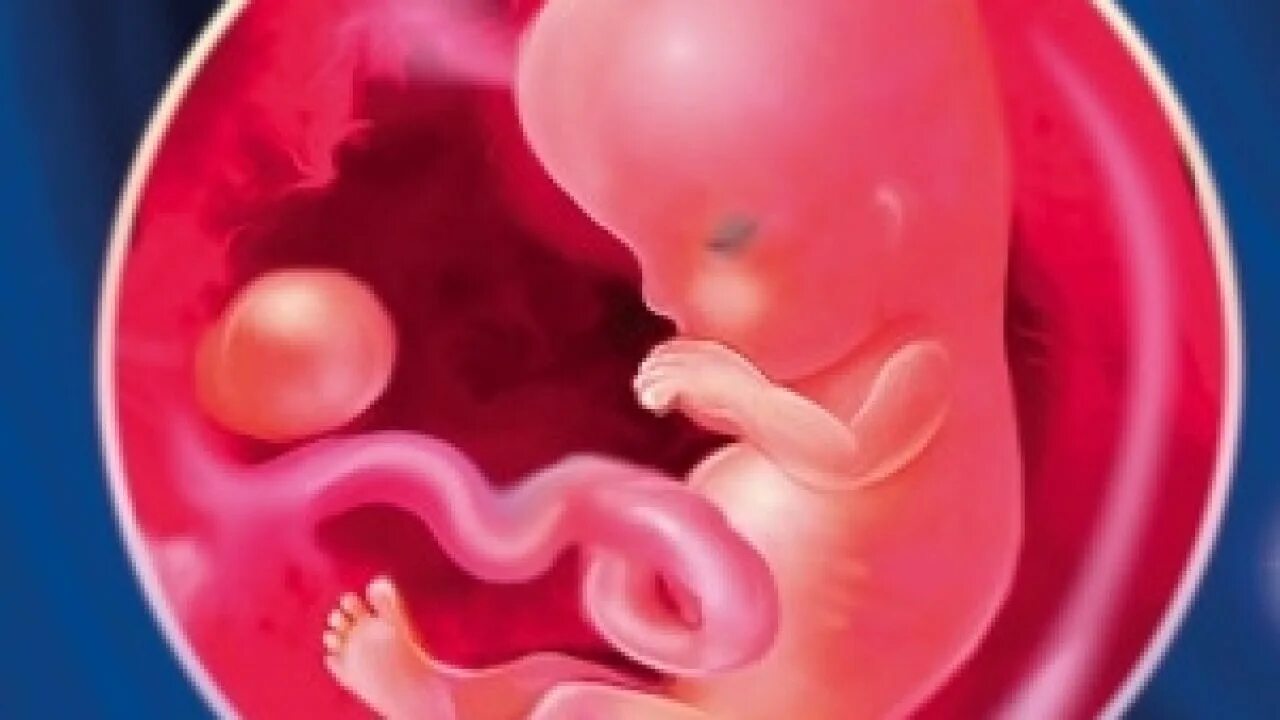

4 неделя берем